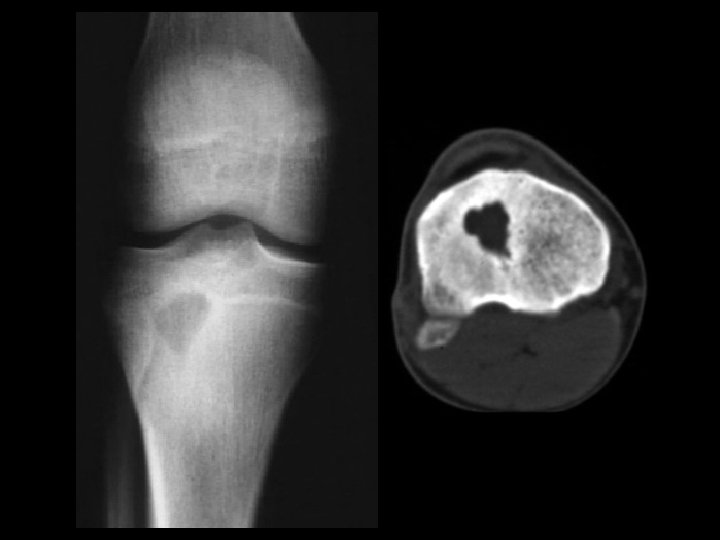

Hemangioma • Findings: – expansile lesion of the proximal tibia containing fine bony septations and a large course calcification – CT scan shows a lacey appearance • ddx: – Paget’s dz – ABC